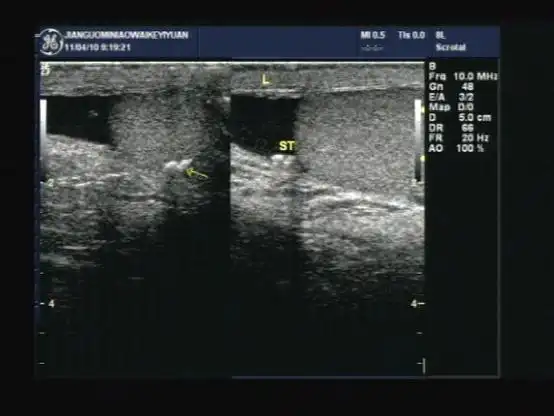

立竿见影精准排雷高危老年胆囊炎患者救治介入超声解难题

b超"回声"大揭秘:胆结石是怎么被发现的?_超声_图像_反射

黄色肉芽肿性胆囊炎